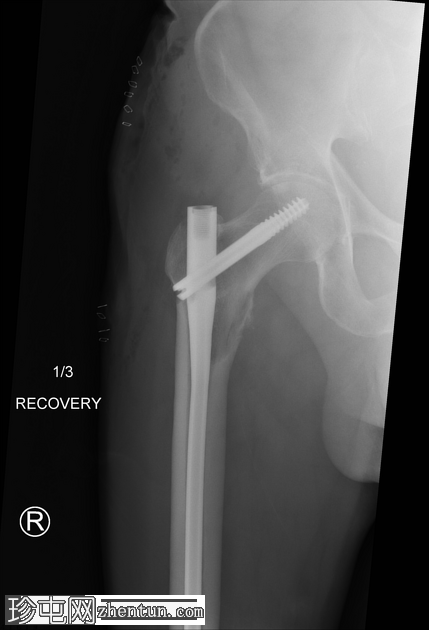

X光片

2.jpeg

正面

右侧髓内钉近端骨折(位于拉力螺钉孔位)。

空心髋螺钉组件完好。

股骨转子间骨折延伸至股骨近端转移灶,小转子粉碎。

以下为既往(及随访)影像学检查结果,供参考,展示术前股骨近端溶骨性病变、髓内钉骨折前的表现以及髓内钉骨折后的治疗情况。